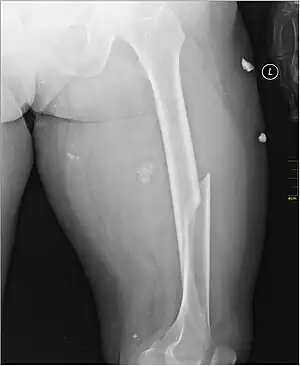

| X-ray image of a femoral shaft fracture | |

A femoral fracture is a bone fracture that involves the femur.[1] They are typically sustained in high-impact trauma, such as car crashes, due to the large amount of force needed to break the bone. Fractures of the diaphysis, or middle of the femur, are managed differently from those at the head, neck, and trochanter

Radiography

Anterior-posterior (AP) and lateral radiographs are typically obtained.[4]